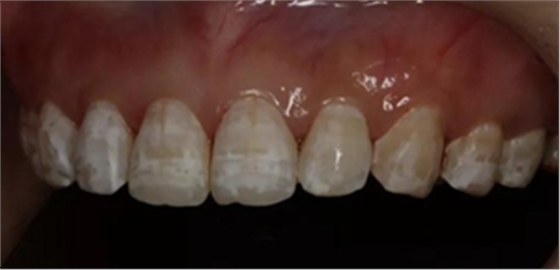

1,術(shù)前照片,全口氟斑牙,前牙表面釉質(zhì)白堊色+黃色斑點(diǎn)+凹坑缺損。

術(shù)前正面?zhèn)让嬲掌?/span>